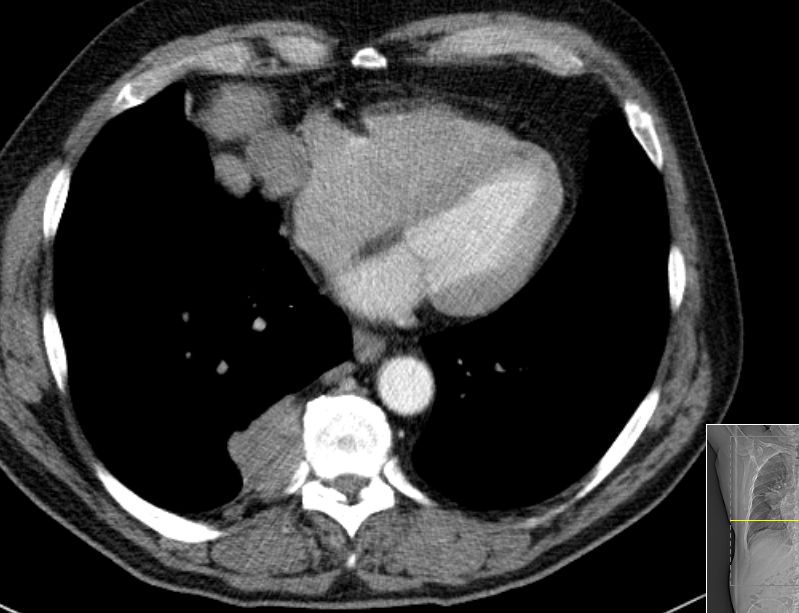

| B1-Thymom | 69-jähriger Mann, bei dem vor einer geplanten orthopädischen Operation eine Lungenaufnahme gemacht wurde. Es fand sich eine Raumforderung im vorderen Mediastinum rechts und ein kleinerer Befund rechts dorsal. Histologische malignes Thymom Stadium IV nach Masaoka. Nach 4 Zyklen Cisplatin, Doxorubicin, Cyclophosphamid partielle Remission. Nach Radikaloperation mit Pneumektomie postoperative Bestrahlung. | |||